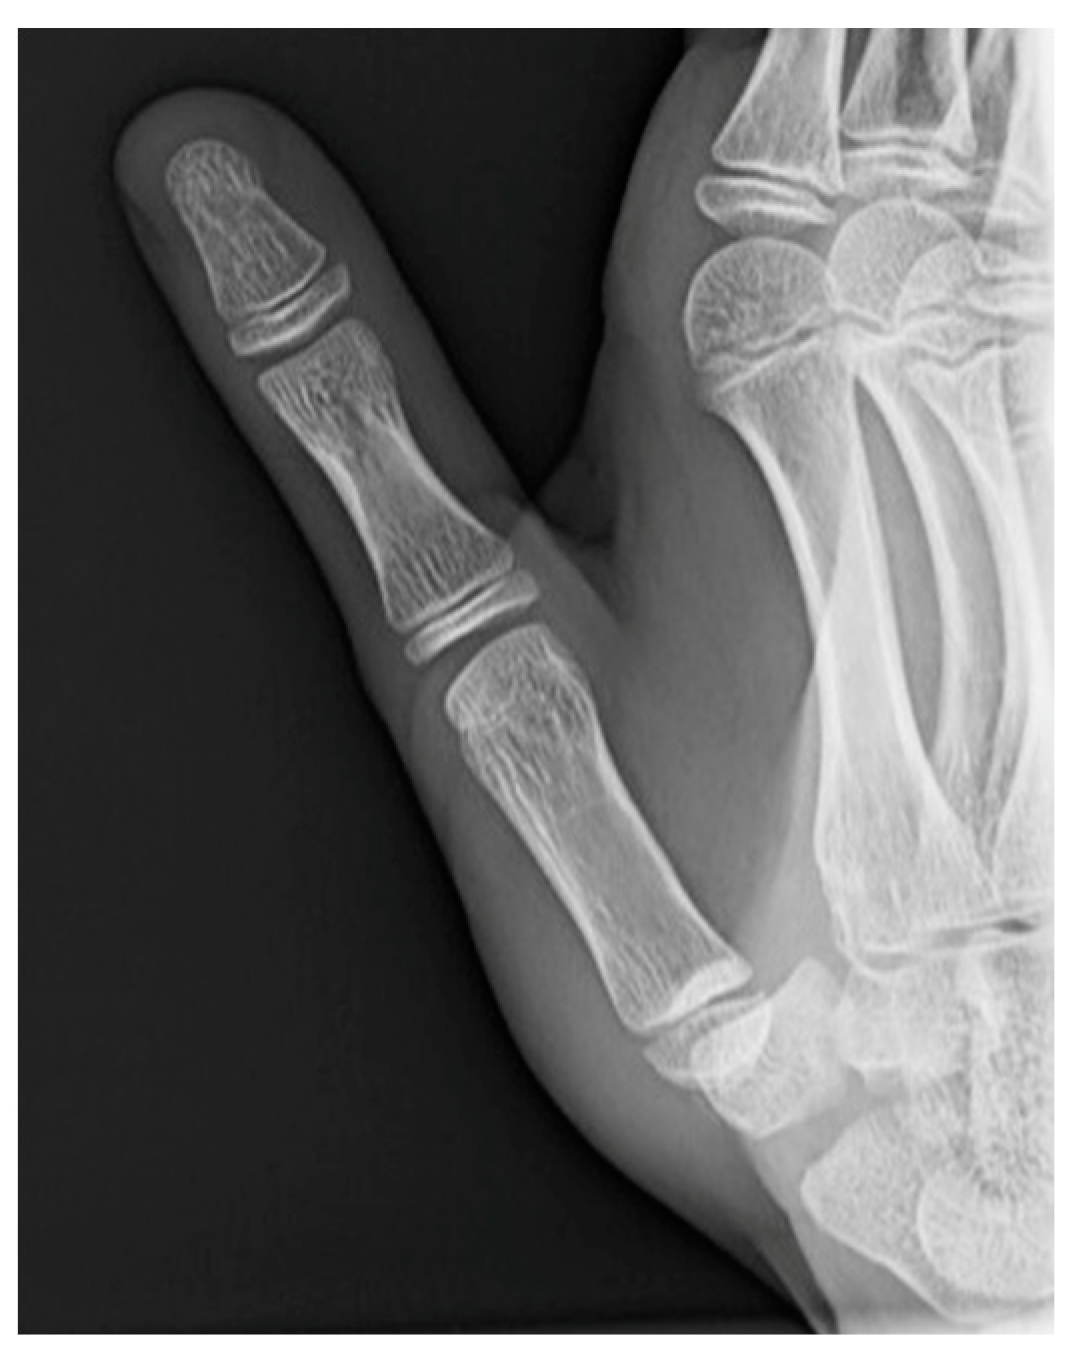

- Roberts projection—strict AP view of the TMC joint. Roberts proposed forced pronation of the wrist and forearm to compensate for the obliquity of the longitudinal axis of the TMC joint in relation to the anatomical axis of the hand. This projection provides a strict profile of the interline of the trapeziometacarpal and scaphotrapezial joints and allows better visualization of the trapezium without carpal superimposition [21] (Figure 2a).